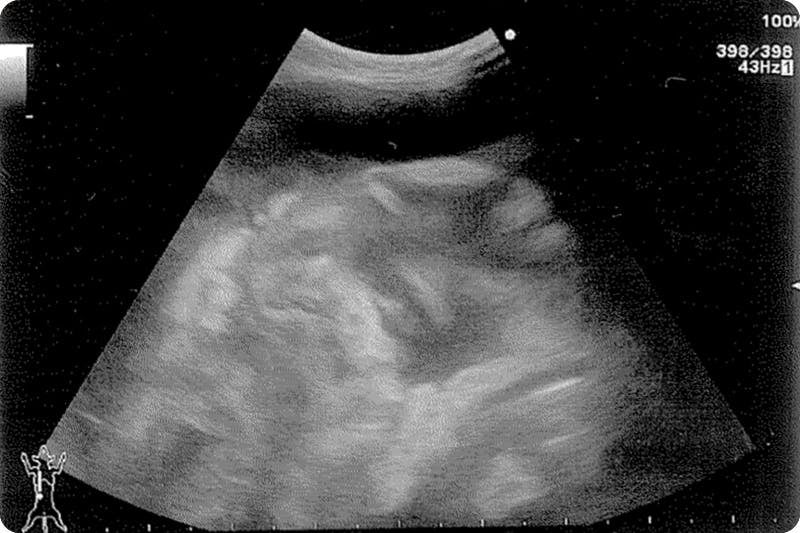

毎日病院で点滴を受け血液検査、レントゲン、エコー、注射を繰り返す日々。

キティの場合ウェットタイプです。

腹水が貯まりパンパンになりました。

9月7日(月) 病院Aにてレントゲン、エコー